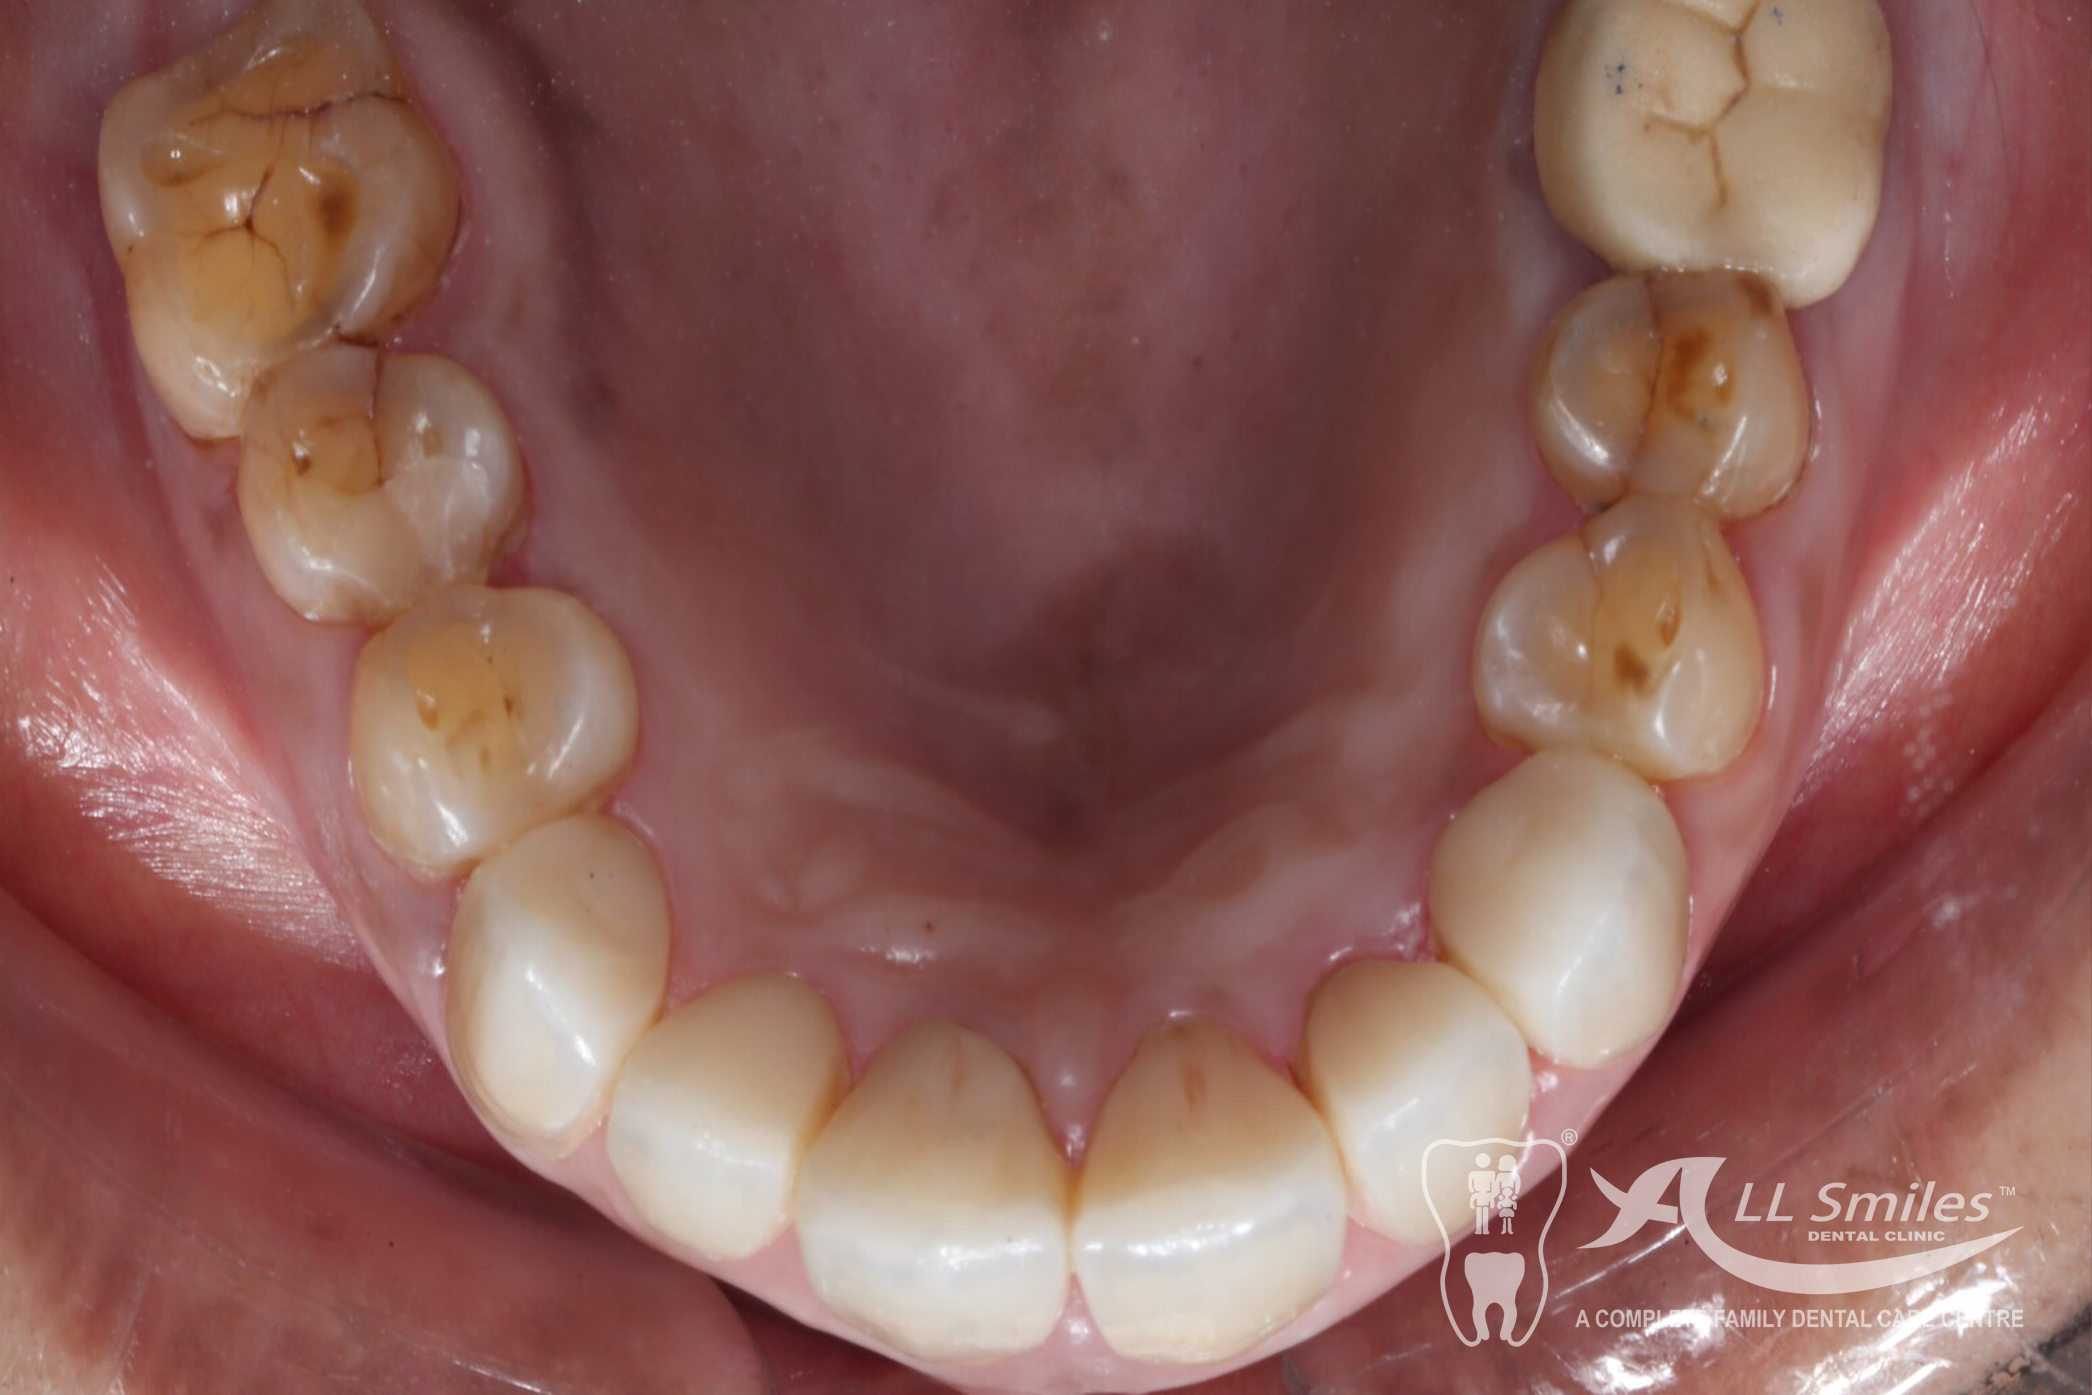

Root Canal Gallery